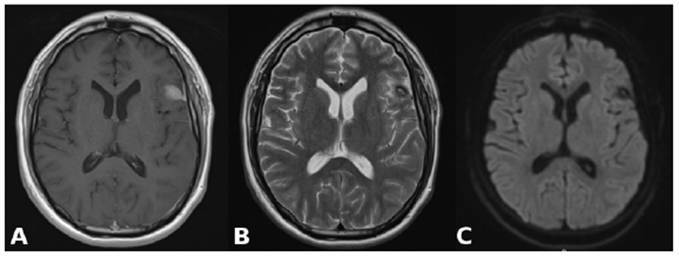

Streptococcus constellatus, a member of the Streptococcus anginosus group, is a commensal bacterium that causes pyogenic infections, particularly abscesses. This report describes the case of a 28-year-old immunocompetent man who developed a brain abscess and epidural empyema after pneumonia. MRI suggested an abscess, which was confirmed by culture, revealing S. constellatus. Treatment included abscess drainage and ceftriaxone administration, which led to a full recovery. Diagnosis is challenging because of overlapping features with other bacteria. Imaging and culturing are crucial for identification. This case highlights the importance of considering S. constellatus in central nervous system infections, even in immunocompetent individuals.